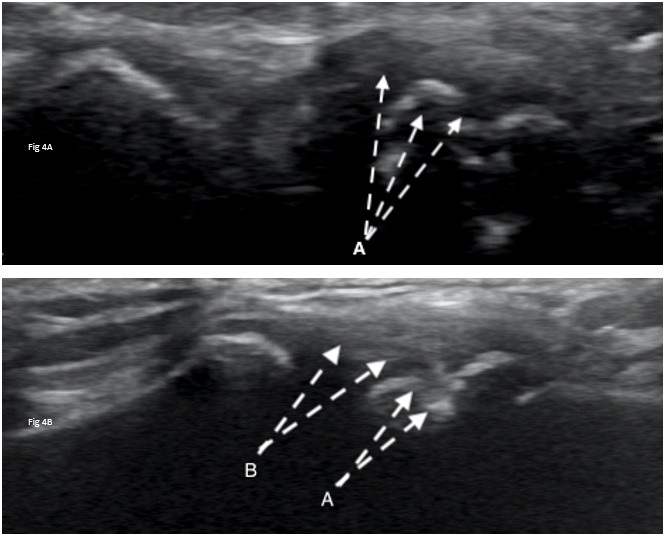

Diagnostic ultrasound imaging (GE Logiq E9; 2010) of the biceps tendons, tendons of the rotator cuff, rotator interval, labrum and anterior/posterior ACJ was performed immediately following the physical examination. Ultrasound confirmed misalignment of ACJ (clavicular portion elevated) with distinct hypoechoic patterns noted on both the clavicular and acromial attachments of the capsule, with associated bony abnormalities (Figure 3A, 4A). Further, a small supraspinatus myotendinous partial thickness tear was also identified. The labrum was not adequately visualized with the ultrasound study.

At the one-year follow-up, the subject reported no pain (NPRS=0/10) and full return to athletics (QDASH =0% disability). A follow-up MRI at one year revealed no discrete labral tears, minimal supraspinatus tendinopathy, and normal visualization of the ACJ (Figure 5B). Similarly, a one-year follow-up diagnostic ultrasound revealed normal appearance of the supraspinatus tendon, its myotendinous junction and ACJ (Figure 3B, 4B).